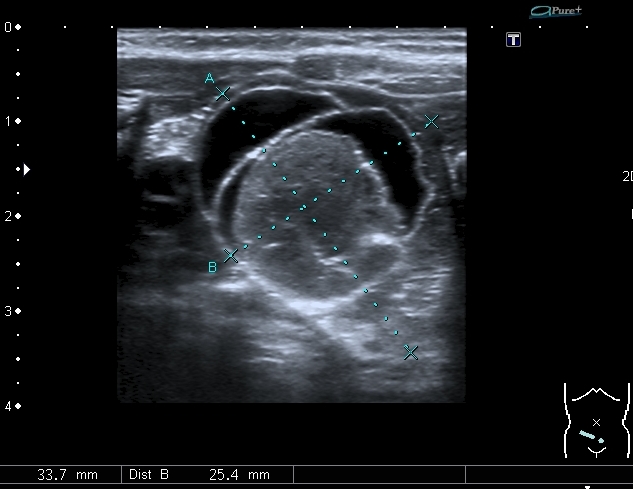

У девочки 5 месяцев ранее на УЗИ нашли образование в полости таза . С заключением киста яичника направлена к нам.

На УЗИ справа от мочевого пузыря - солидно - кистозное образование около 3 см. Образование прилежит к правому яичнику, который визуально не изменён, но смещается относительно его при движениях брюшной стенки Относительно яичника образование гиповаскулярное Выставил диагноз объёмного образования полости таза (дифференцировать энтерокистому и дермоид). Не думаю, что образование исходит из яичника, поэтому стартую тему в гастроэнтерологических исследованиях.